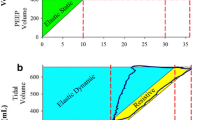

All animal experiments were approved by the “Niedersächsisches Landesamt für Verbraucherschutz und Lebensmittelsicherheit” (LAVES, Oldenburg, Lower Saxony, Germany, approval number 17/2068) which house the German equivalent of an institutional animal care and use committee, according to the European Animal Welfare Regulations. After randomization, male rats (Fisher 344/DuCrl, Charles River, Sulzfeld, Germany) were either treated intratracheally with Bleomycin (Group B; Dosage: 4.5 U/kg bodyweight, n = 20) or not (Group H, healthy, n = 17). This dosage of Bleomycin has been shown to result in subclinical lung injury at day 1, meaning that clinical presentation, oxygen saturation and tissue elastance measurements are not substantially different from healthy controls (Lutz et al. 2015; Knudsen et al. 2018; Albert et al. 2020). At day 1, animals were further randomized into three subgroups characterized by different mechanical ventilation protocols. The groups H/no-ventil (n = 6) and B/no-ventil (n = 6) were not ventilated and represented the baseline situation before entering mechanical ventilation. The other groups were invasively ventilated for 3 h with either PEEP = 1 cmH2O [groups H/PEEP1 (n = 5) and B/PEEP1 (n = 7)] or PEEP = 5 cmH2O [groups H/PEEP5 (n = 6) and B/PEEP5 (n = 7)]. The tidal volume was 10 ml/kg bodyweight room air, the respiratory rare 90/min and the inspiratory-to-expiratory ratio was 1:2. At the beginning of mechanical ventilation, and every 60 min during mechanical ventilation, recruitment maneuvers consisting of an increase of the airway opening pressure to 30 cmH2O were performed. After mechanical ventilation, two pressure-controlled pressure–volume (PV) loops were recorded to calculate the quasistatic compliance (Cst). For this purpose, the airway opening pressure was increased stepwise with a step size of 3.86 cmH2O from an onset airway opening pressure of 3–30 cmH2O. Afterwards, the pressure deceased with the same step size from 30 to 3 cmH2O. The displaced air volume was determined and using the Salazar–Knowles equation the slope of the PV loop at 5 cmH2O on expiration was computed to determine Cst (Salazar and Knowles 1964). The procedures regarding the mechanical ventilation were as follows: the rats were anesthetized with an intraperitoneal injection of Ketamine (80 mg/kg bodyweight) combined with Xylazine (5 mg/kg bodyweight). Afterwards, a tracheotomy was performed and the animals were connected to the newFlexiVent rodent ventilator (SCIREQ®, Montreal) and mechanically ventilated as described above. During mechanical ventilation narcosis was maintained by means of 1% isoflurane in room air combined with subcutaneous injection of 2 mg/kg bodyweight butorphanol (Torbugesic®).

Based on these qualitative observations, we quantified the composition of the interalveolar septa and the thickness of the blood–gas barrier. The data are summarized in Table 2 and visualized in part in Fig. 2. The statistical analyses took the factors bleomycin pre-treatment and the mechanical ventilation into consideration. Neither bleomycin pre-treatment nor mechanical ventilation had a significant effect on the volume of AE cells within interalveolar septa, V(AE,sep). The surface area of air-covered AE1 cells, S(AE1,sep), was reduced by bleomycin pre-treatment; while ventilation did not show an effect. The surface area of AE2 cells covered by air S(AE2,sep) was unaffected by bleomycin pre-treatment and mechanical ventilation. The absolute volume of the interstitium within interalveolar septa was significantly increased due to bleomycin pre-treatment (Table 2). The adjustment of the p value by means of Tukey post hoc test illustrated a significantly higher V(inter,sep) in B/PEEP1 compared to B/PEEP5; while, there were no differences between B/no-ventil and B/PEEP5 (Fig. 2a). Since the interstitium consists of interstitial cells (IC) and extracellular matrix (ECM) which can further be distinguished in collagen fibrils (col) and ECM other than collagen fibrils (restECM), the volumes of these components were analyzed further. Neither bleomycin pre-treatment nor mechanical ventilation had an effect on V(ECM,sep) (Table 2). On the other hand, bleomycin-induced lung injury resulted on day 1 after instillation already in an increase in the volume of interstitial cells (Fig. 2b; V(IC,sep)) and this increase was most pronounced in B/PEEP1 so that the increase in V(inter,sep) at the organ scale was primarily a consequence of an increase in the volume of interstitial cells within septa rather than an increase in the volume of extra cellular matrix. Finally, the capillary network within the interalveolar septa was analyzed. This included the quantification of the volumes of endothelial cells (V(endo,sep)) and capillary lumen (V(caplumen,sep)) as well as the surface area of the endothelial cells (S(endo,sep)). None of these parameters was affected by bleomycin pretreatment or mechanical ventilation. The volume of the blood–gas barrier and its surface areas at the air and blood side were used to determine the arithmetic mean thickness of the blood–gas barrier \(\tau\)(bgb). \(\tau\)(bgb) was increased as a result of the bleomycin pre-treatment and this increase was most pronounced in B/PEEP1 so that the Tukey post hoc test for adjustment of the p level revealed that, within the B group, \(\tau\)(bgb) was significantly higher in B/PEEP1 compared to B/PEEP5 (Fig. 2c). Dividing the blood–gas barrier into its components, alveolar epithelium, interstitium and endothelium, reveals that the increase in barrier thickness was mainly a result of the increase in the thickness of the interstitial layer \(\tau\)(inter). This alteration was most pronounced in the bleomycin groups where \(\tau\)(inter) was elevated in B/PEEP1 compared to B/PEEP5 (Fig. 2d). With regard to the thickness of the endothelial layer \(\tau\)(endo), there was a significant effect assigned to the bleomycin pretreatment but the Tukey post hoc test did not reveal differences between the subgroups.

Stereological data characterizing abnormalities of the blood–gas barrier. Bleomycin challenge increases the absolute volume of the interstitium within the interalveolar septa (a), in particular after mechanical ventilation with PEEP = 1 cmH2O. The increase in V(inter,sep) is predominantly attributable to an increase in the volume of interstitial cells (b) and results in an increase in the total arithmetic mean thickness of blood–gas barrier (c). In (d) the arithmetic mean thickness of the interstitium is shown. Statistical analyses are based on a two-way ANOVA taking the factors “bleomycin pre-treatment” and “mechanical ventilation” into account. Statistically significant differences after adjustment of the p level for multiple testing using Tukey correction is indicated as follows:*p < 0.05